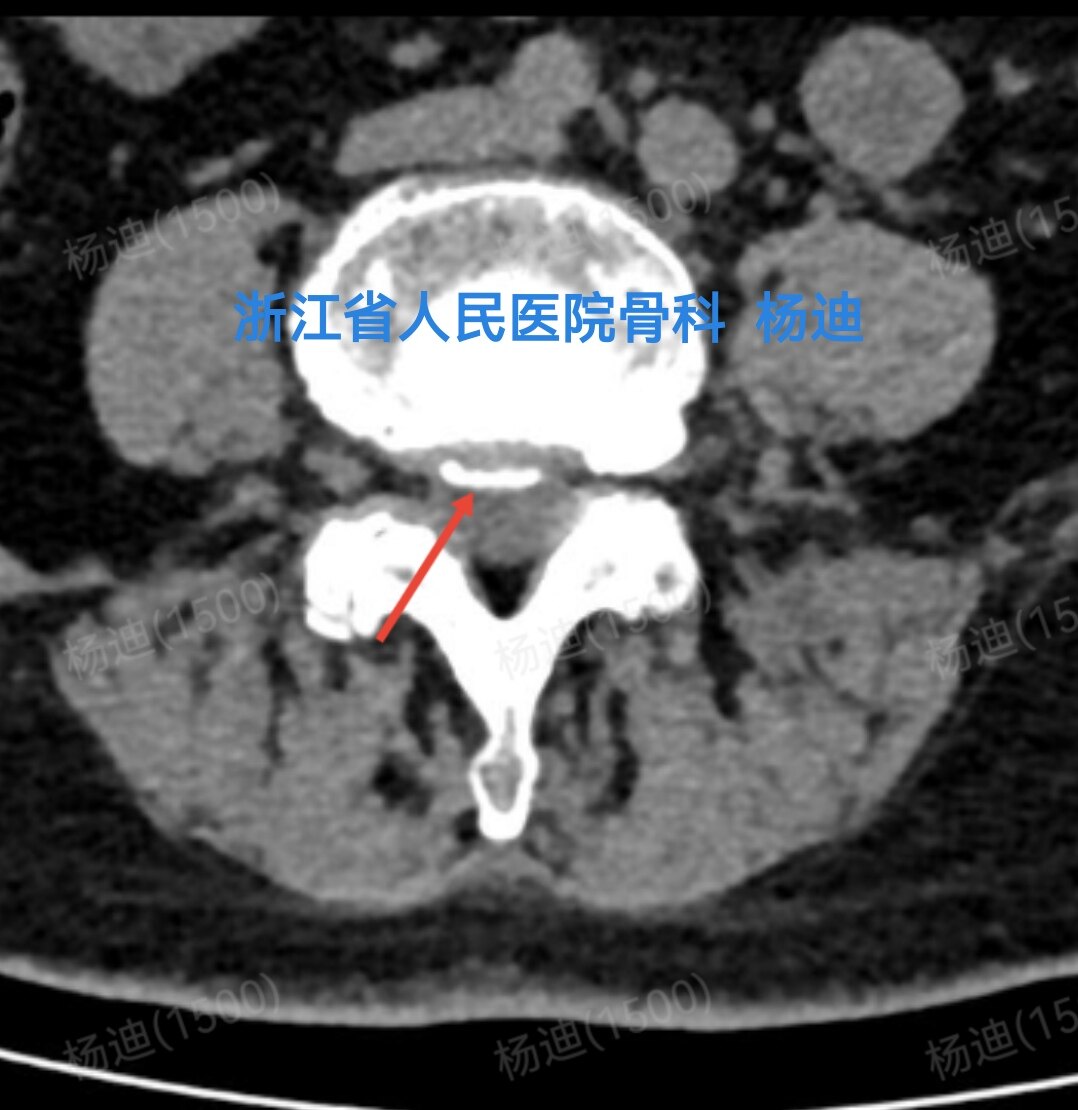

图为磁共振横断面检查结果,提示腰4/5椎间盘突出(红色箭头)。

图为CT检查结果,提示腰4/5椎间盘突出、钙化(红色箭头)。